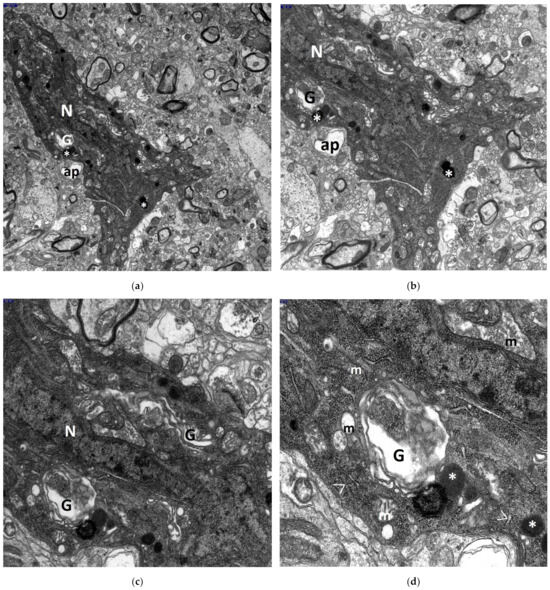

3. Results